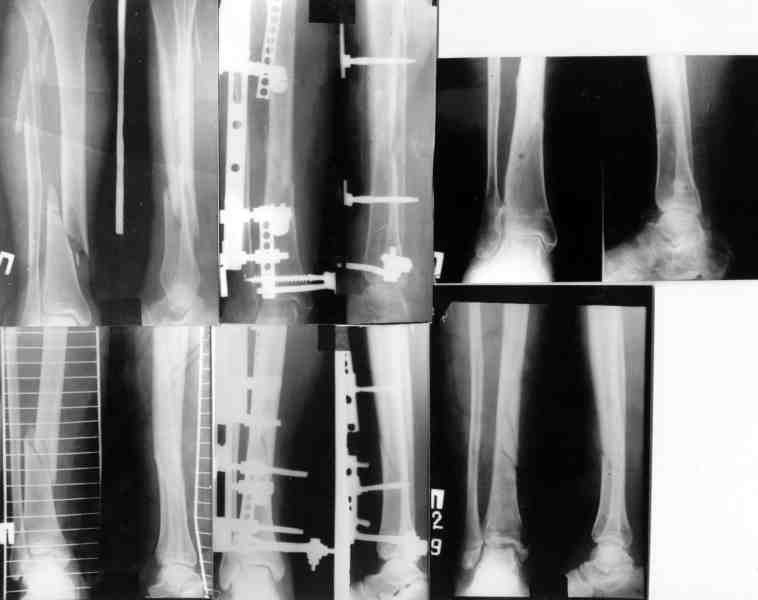

Re: Огнестрельный перелом плеча ( продолжение)

Вот еще информация, ознакамливайтесь pls/